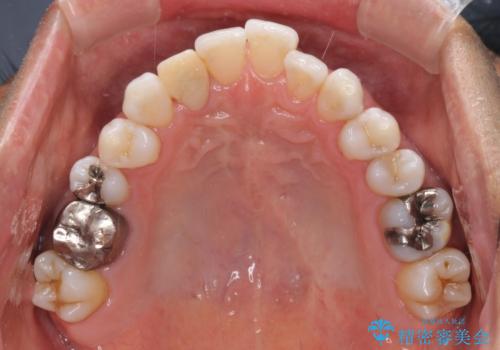

- 治療途中の前歯と上下前歯のデコボコ気にして来院された患者様です。

前歯のデコボコはインビザラインにより歯列を整え、その後に、前歯などをオーダーメイドタイプのオールセラミッククラウンにて補綴治療することとしました。

長時間のマウスピース装着に協力いただき、短期間で歯列をしっかりと改善することができました。

ホームホワイトニングを併用していただいたので、とても明るい口元に仕上がり、患者様には大変満足していただきました。